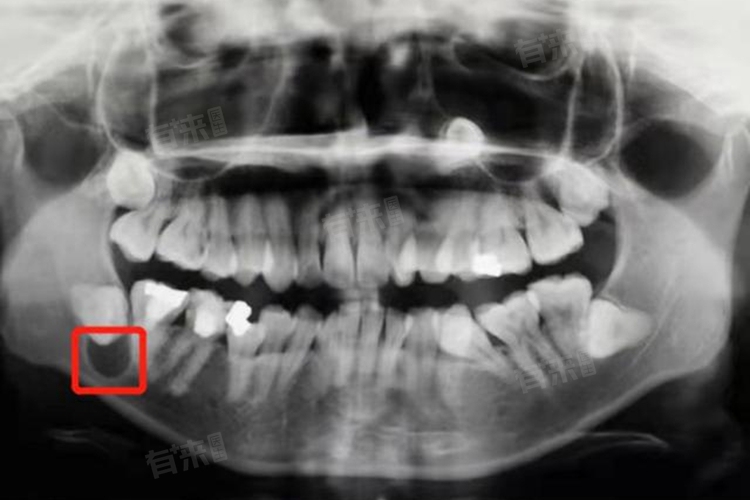

下颌骨囊肿手术千万别去做的说法是不正确且没有科学依据的,若不进行手术,可能会因囊肿增大、破坏骨结构、影响牙齿、增加感染风险甚至恶变而导致严重后果,手术治疗是必要且有益的。

2、破坏下颌骨结构:随着囊肿的发展,会逐渐侵蚀下颌骨,导致骨组织变薄、破坏,影响下颌骨的强度和稳定性,可能出现骨折等严重并发症,手术可以清除囊肿,修复受损的骨组织,恢复下颌骨的正常结构和功能。

3、影响牙齿发育和排列:如果囊肿位于牙齿周围,可能会影响恒牙的萌出和牙齿的排列,导致牙齿畸形,对于儿童患者,早期手术有助于保障牙齿的正常发育,术后需密切观察牙齿生长情况,必要时进行正畸治疗。

手术前应进行全面的身体检查和影像学检查,评估囊肿的大小、位置及与周围组织的关系,制定个性化的手术方案,术后需严格遵守医嘱,保持口腔卫生,避免剧烈运动,定期复诊检查伤口愈合情况。